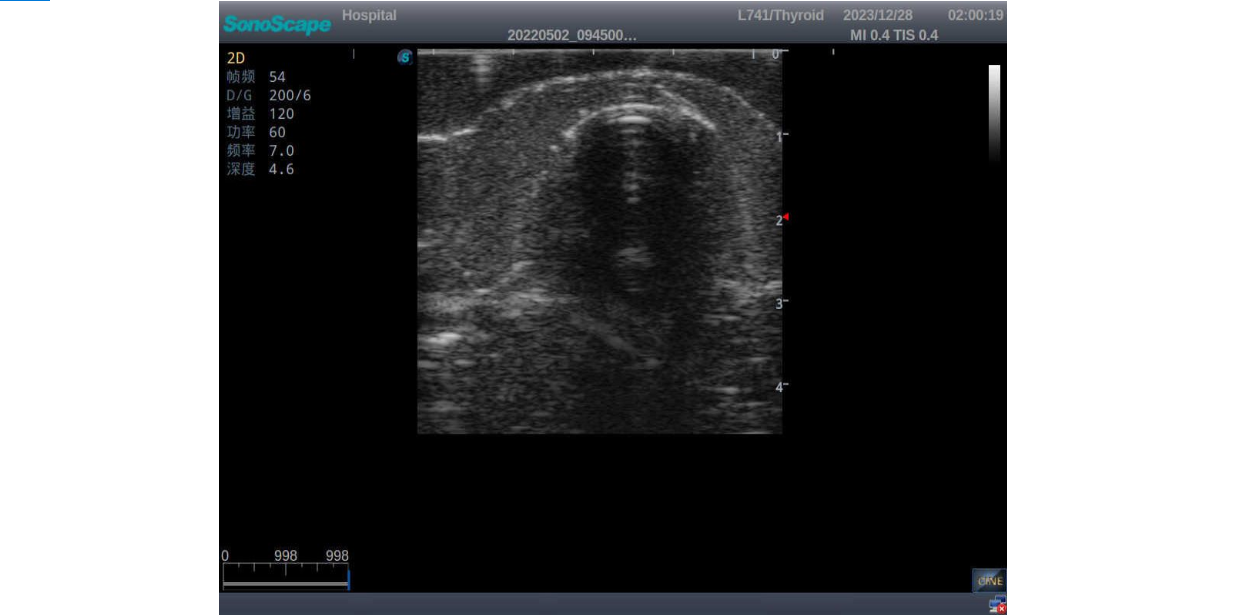

3)       It comes with four (4) thyroid modules and can show five (5) ultrasonic images: normal thyroid, thyroid adenoma, thyroid cancer, nodular goiter, thyroid cyst

Nodular goiter with irregular border and varying sizes of low echo, isoechoic, or high echo nodules